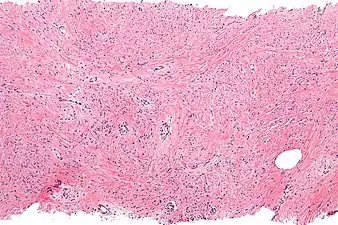

| Micrograph of mammary myofibroblastoma. H&E stain. | |

Medical imaging may suggest but cannot prove that a tumor is MFB. Mammography, computed tomography scans, and magnetic resonance imaging of mammary[1][12] and extramammary[1][13] MFB typically show well-defined and well-circumscribed tumors which in almost all cases have no calcifications; these results suggest that the tumor is not malignant but do not indicate which type it might be. The diagnosis of MFB depends on the microscopic histopathology (i.e. appearances after proper tissue preparation and staining) of its pre-surgery biopsied issues. As shown in the upper image and the two images in the Additional images section seen below, both mammary and extramammary MFB tissues contain spindle cells, variable numbers of adipocytes (i.e. fat cells) and broad sheets or, less often, thick bundles of collagen fibers.[5] About 4% of cases have an epithelial tumor cell-like morphology,[5] i.e. the tissues are composed predominantly of epithelioid cells variably mixed with a minority (10% to 40%) of round, polygonal, and spindle-shaped cells.[19] Unlike malignant tumors, MFB tumors do not have: a) atypical cells except in the rare cases which contain small clumps of multinucleated cells; b) rapidly proliferating cells as defined by measuring the proliferative index (i.e. fraction of cells undergoing mitosis); or c) areas of necrosis (i.e. areas of dead or dying cells).[16] Microscopy of tumors in the spindle cell lipoma tentative variant of MFB show a mixture of mature fat cells, ropey collagen, and spindle cells in a myxoid (i.e. background connective tissue that stains blue or purple rather than the red of normal connective tissue) matrix.[18] The blood vessels in these tumors often appear hyalinized.[16] Tumor tissues in the tentative cellular angiofibroma variant of MFB contain spindle cells in all cases, fat cells in ~50& of cases, mast cells, peri-vascular infiltrates of lymphocytes, pleomorphic cells in some cases, and cells with some features of the malignant sarcoma cells in sarcoma tumors in rare cases. (The presence of these sarcoma-like cells does not seem to impact the prognosis of this variant.) All of these cells are in edematous-to-fibrous stromatous tissue.[16]